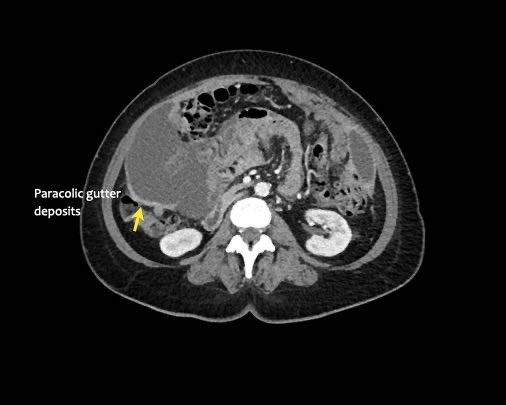

Rãnh cạnh đại tràng

Bất kỳ vị trí nào trong ổ bụng được phủ bởi phúc mạc đều có thể là đích đến của các nốt cấy ghép phúc mạc.

Các vị trí điển hình khác bao gồm rãnh cạnh đại tràng, túi cùng trực tràng-bàng quang hoặc trực tràng-tử cung, dây chằng liềm và mặt bụng của cơ hoành.